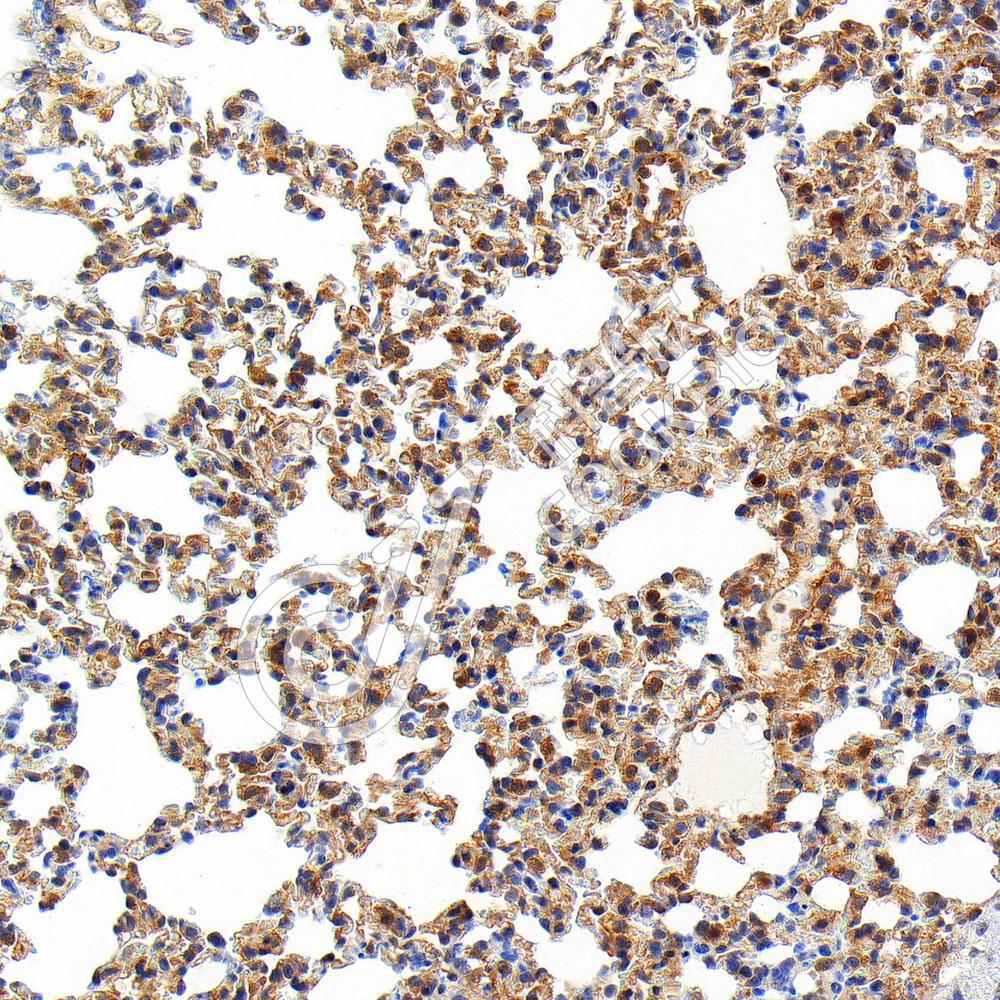

IHC检测NF-κB p65蛋白(货号 K547991).

样品: 小鼠损伤肺, 4%多聚甲醛 (货号KSG1101) 固定12-24小时.

抗原修复: 柠檬酸抗原修复液(干粉, pH 6.0) (KSG1201), 高压锅均匀喷气计时2分钟.

—抗: 1: 6300稀释, 4℃ 孵育过夜.

二抗: S-vision免疫组化多聚二抗(山羊抗兔),即用型 (货号KB3906), 室温孵育20分钟.